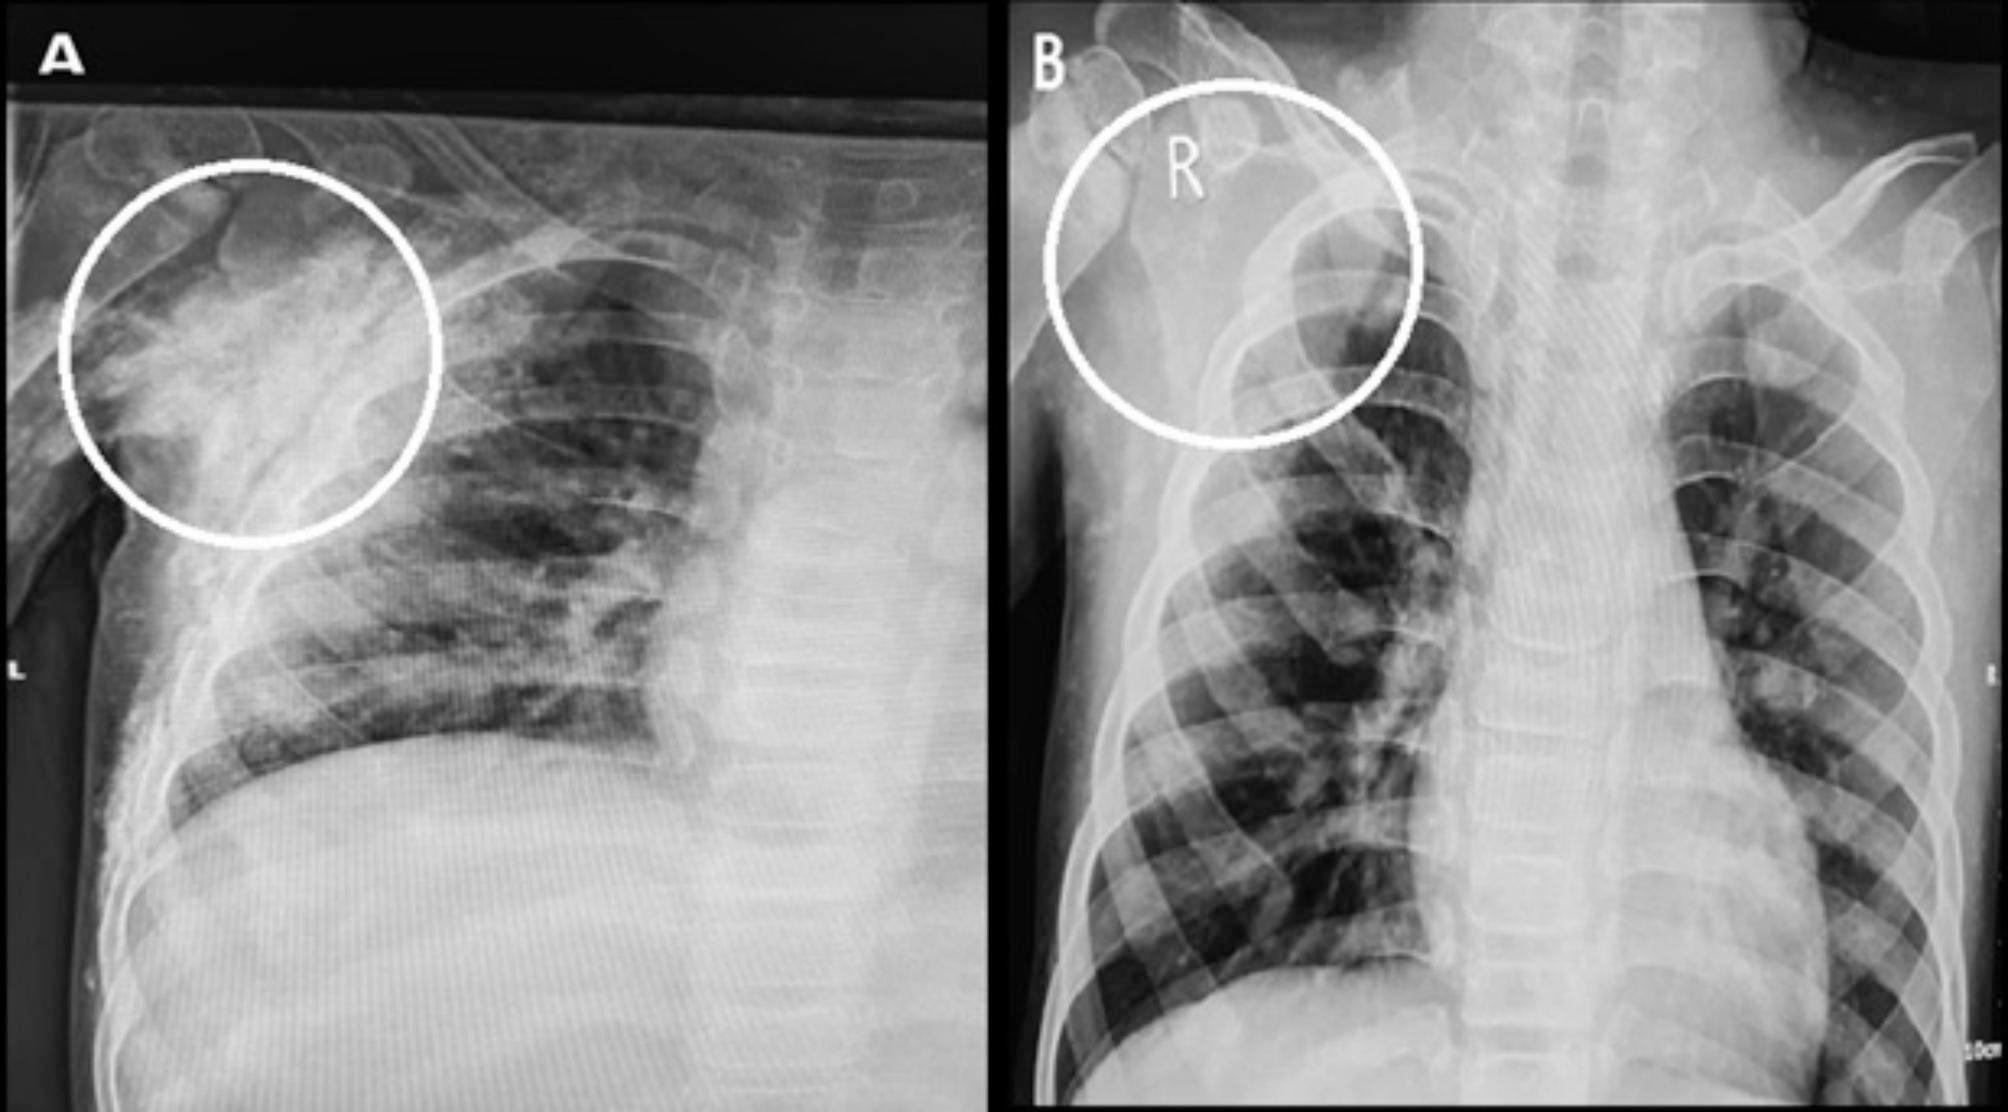

In this clinical trial, five patients diagnosed with JDM and calcinosis lesions were enrolled. The primary treatment consisted of weekly infliximab injections for 16 weeks, targeting all four sides of each lesion. Lesion dimensions, including length and width, were documented and monitored weekly. Before the intervention, patients underwent radiographic imaging. After the final injection in week 16, a follow-up radiographic assessment was performed. Data were analyzed using the Generalized Estimating Equation (GEE) method.

The lesions' size significantly decreased in both length and width during each visit. On average, the lesion length reduced by 2.66%, and the width shrank by 3.32% per visit. Based on radiographic findings, the average length and width of lesions at the initial visit were 12.09 ± 5.05 mm (range: 6.00-25.50 mm) and 6.35 ± 3.00 mm (range: 2.00-16.00 mm), respectively. The average length and width at the last visit were 5.59 ± 7.05 mm (range: 0-23.00 mm) and 3.41 ± 4.05 mm (range: 0-13.00 mm), respectively. No specific side effects related to the treatment were reported.